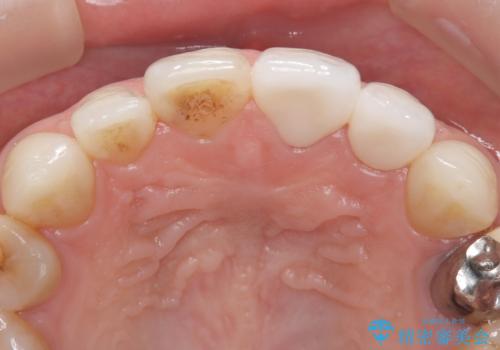

- 「前歯の色が気になる」を主訴に来院された患者さんです。以前他院にて、前歯2本をCR(プラスチック)で治療されていたところが劣化し変色していました。歯の長さも左右で異なっている状態でした。大部分がCR(プラスチック)修復されていたので、オールセラミッククラウンで治療を行いました。

古いCR(プラスチック)とその下の虫歯を除去した後に新しい土台を立てています。適合が良い被せ物を作るために拡大鏡を使用しながら歯を削り、変形のほとんどないシリコンという材料で型取りを行っています。